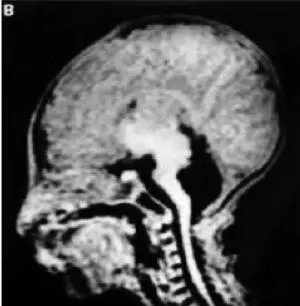

Рис. 18. Схема гена человека, кодирующего инсулин (Garin I. et al., 2010) [81].Схема человеческого гена, кодирующего инсулин с указанием расположения мутаций при гомозиготном или гетерозиготном наследовании у пробандов с сахарным диабетом. Мутации с участием кодирующих областей приведены выше гена, с участием некодирующих областей ниже гена. Белки в кодирующих областях гена, обозначены серым цветом, а регионы кодирования 5\'— и З\'-нетранслируемой области мРНК инсулина — желтым цветом. Красным и черным цветом обозначены мутации, обнаруженные у пробандов с транзиторным и перманентным сахарным диабетом новорожденных, соответственно. Экзон 2 кодирует 1-62 аминокислоты, а 3 экзон — 63-110 аминокислоты в молекуле препроинсулина

Garin I. et al. [81] в 2010 году сообщили о рецессивных мутациях в гене, кодирующем инсулин, что приводило к развитию неонатального сахарного диабета. Эти мутации влияют на биосинтез проинсулина и функционируют как нулевые мутации. Одна мутация приводит к удалению из гена инсулина экзонов 1 и 2. Есть несколько мутаций, расположенных в промоторной области гена, которые приводят к снижению транскрипции. Мутации в области кодирования З’-нетранслируемой области мРНК влияют на стабильность мРНК. Другие мутации затрагивают инициацию трансляции мРНК инсулина или приводят к синтезу усеченной молекулы проинсулина (рис. 18).